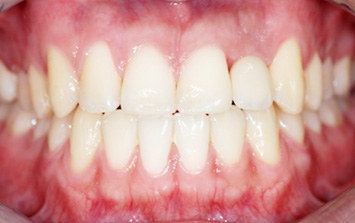

앞니 상실과 보철물 오염으로 내원한 환자분. 오른쪽 오염된 보철물로 인하여 잇몸이 올라간 상태, 치주치료와 올세라믹 치료를 하고

상실된 부위에 임플란트를 식립 하였습니다. 앞니의 경우 외모를 결정시키는 중요한 의미가 있기 때문에

자연치아와 구별 안될 정도로 자연스럽게 만들어 드렸습니다.